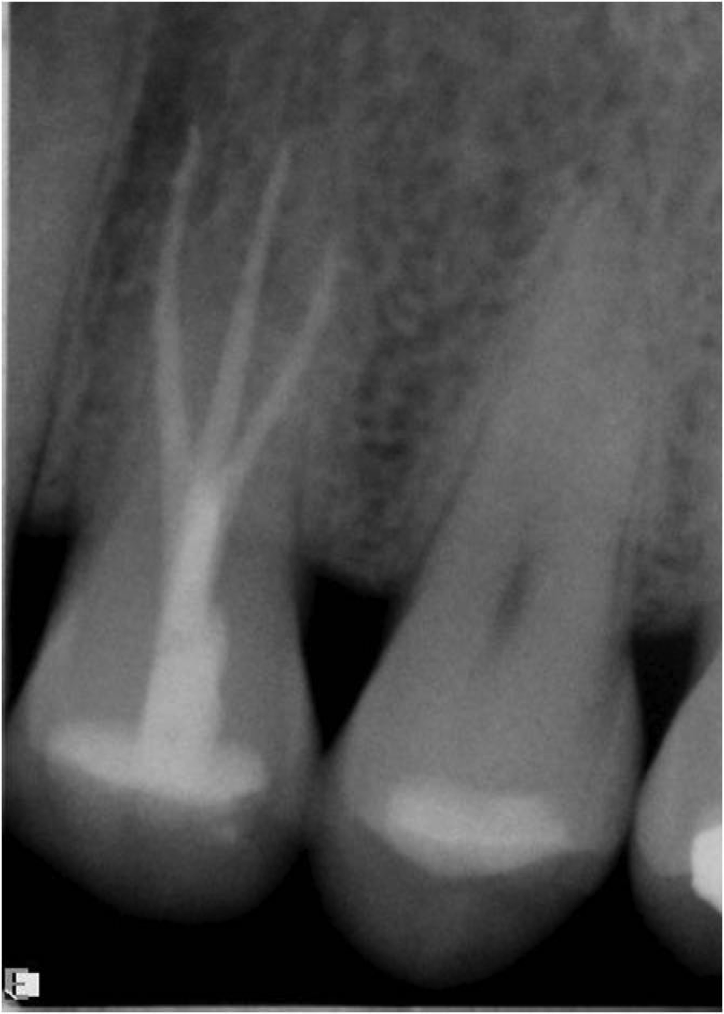

Excellent diagnosis essentially begins with two fundamental components: a doctor willing to listen to the patient’s chief complaint, and proper diagnostic tools. Among the most important tools are a precise periapical radiograph (PA) and bitewing (BW). Although a PA is often enough to provide an accurate portrayal of the patient’s condition, sometimes it alone does not suffice. Figure 1, Figure 2, and Figure 3 demonstrate a case that illustrates this point clearly. Despite two acceptable PAs (Figure 1 and Figure 2), it is difficult to assess the source of the patient’s pain to temperature. However, the BW radiograph Figure 3 provides significantly more clarity than either of the two PAs. The BW depicts localized bone loss (around tooth No. 2), a pulp stone (No. 2), a flat occlusion, numerous calcified canals, multiple restorations in tooth No. 30, and gross decay especially on tooth No. 3, which is the source of the patient’s pain to temperature. In this instance these images depict how much more useful a BW can be than just a conventional PA.